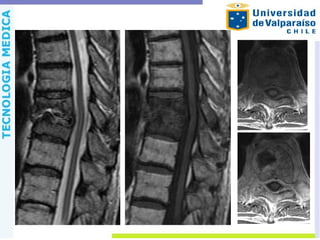

Espondilodiscitis Compromiso infeccioso delcuerpo y disco intervertebral, por diseminación hematógena, a través del plexo venoso de Batson o por contigüidad. Lo más frecuente es la afectación de la columna lumbar, en varones entre 50-70 años y con presencia de S. aureus.

RM Sensibilidad 96%. Exactitud94% Las características incluyen o Discos de alta señal en T2 o Cuerpos vertebrales de baja señal T1 o Realce de contraste de los discos y los cuerpos vertebrales o Realce de contraste de la masa de tejidos blandos paravertebrales o Realce de contraste de absceso paravertebral del psoas o Realce de contraste de absceso epidural